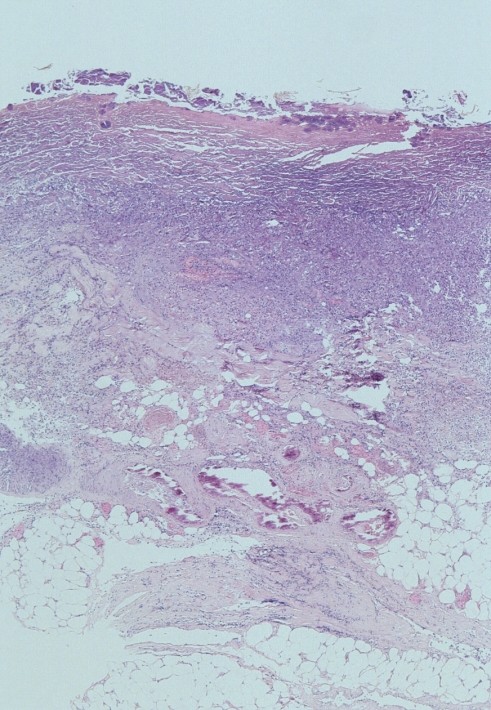

kleine en medium-size arteriën. De kalkafzettingen kunnen in een huidbiopt

worden gezien in en ook rond de vaten in de dermis en subcutis. Op

![Calciphylaxis cutis bij nierinsufficiëntie en secundaire hyperparathyreoïdie (click on photo to enlarge) [source: www.huidziekten.nl] Calciphylaxis cutis bij nierinsufficiëntie en secundaire hyperparathyreoïdie](../../../images/calciphylaxis-1z.jpg) |

![Calciphylaxis cutis bij nierinsufficiëntie en secundaire hyperparathyreoïdie (click on photo to enlarge) [source: www.huidziekten.nl] Calciphylaxis cutis bij nierinsufficiëntie en secundaire hyperparathyreoïdie](../../../images/calciphylaxis-2z.jpg) |

| calciphylaxis cutis |

calciphylaxis cutis |